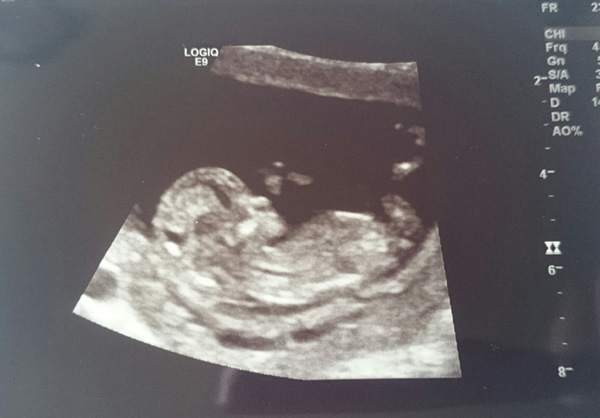

Hi, here are a few pics from my 12 week scan. I'm not sure if I can make out a nub but a few people think they can. Anyone have any guesses from nub and skull theories?? Thanks so much :)

Can't say I see a nub but I think I get a girly vibe from these...

The skull definitely looks quite different to my son's ultrasound pics. His head looked bigger and more angular. I hope that's a sign this could be a little girl. Trying not to get carried away though...

Maaaybe girl but not great pics and 12w is still early.

12 weeks is so early still. I'm going to guess boy.

Girly skull, but I can't see a nub. FX!